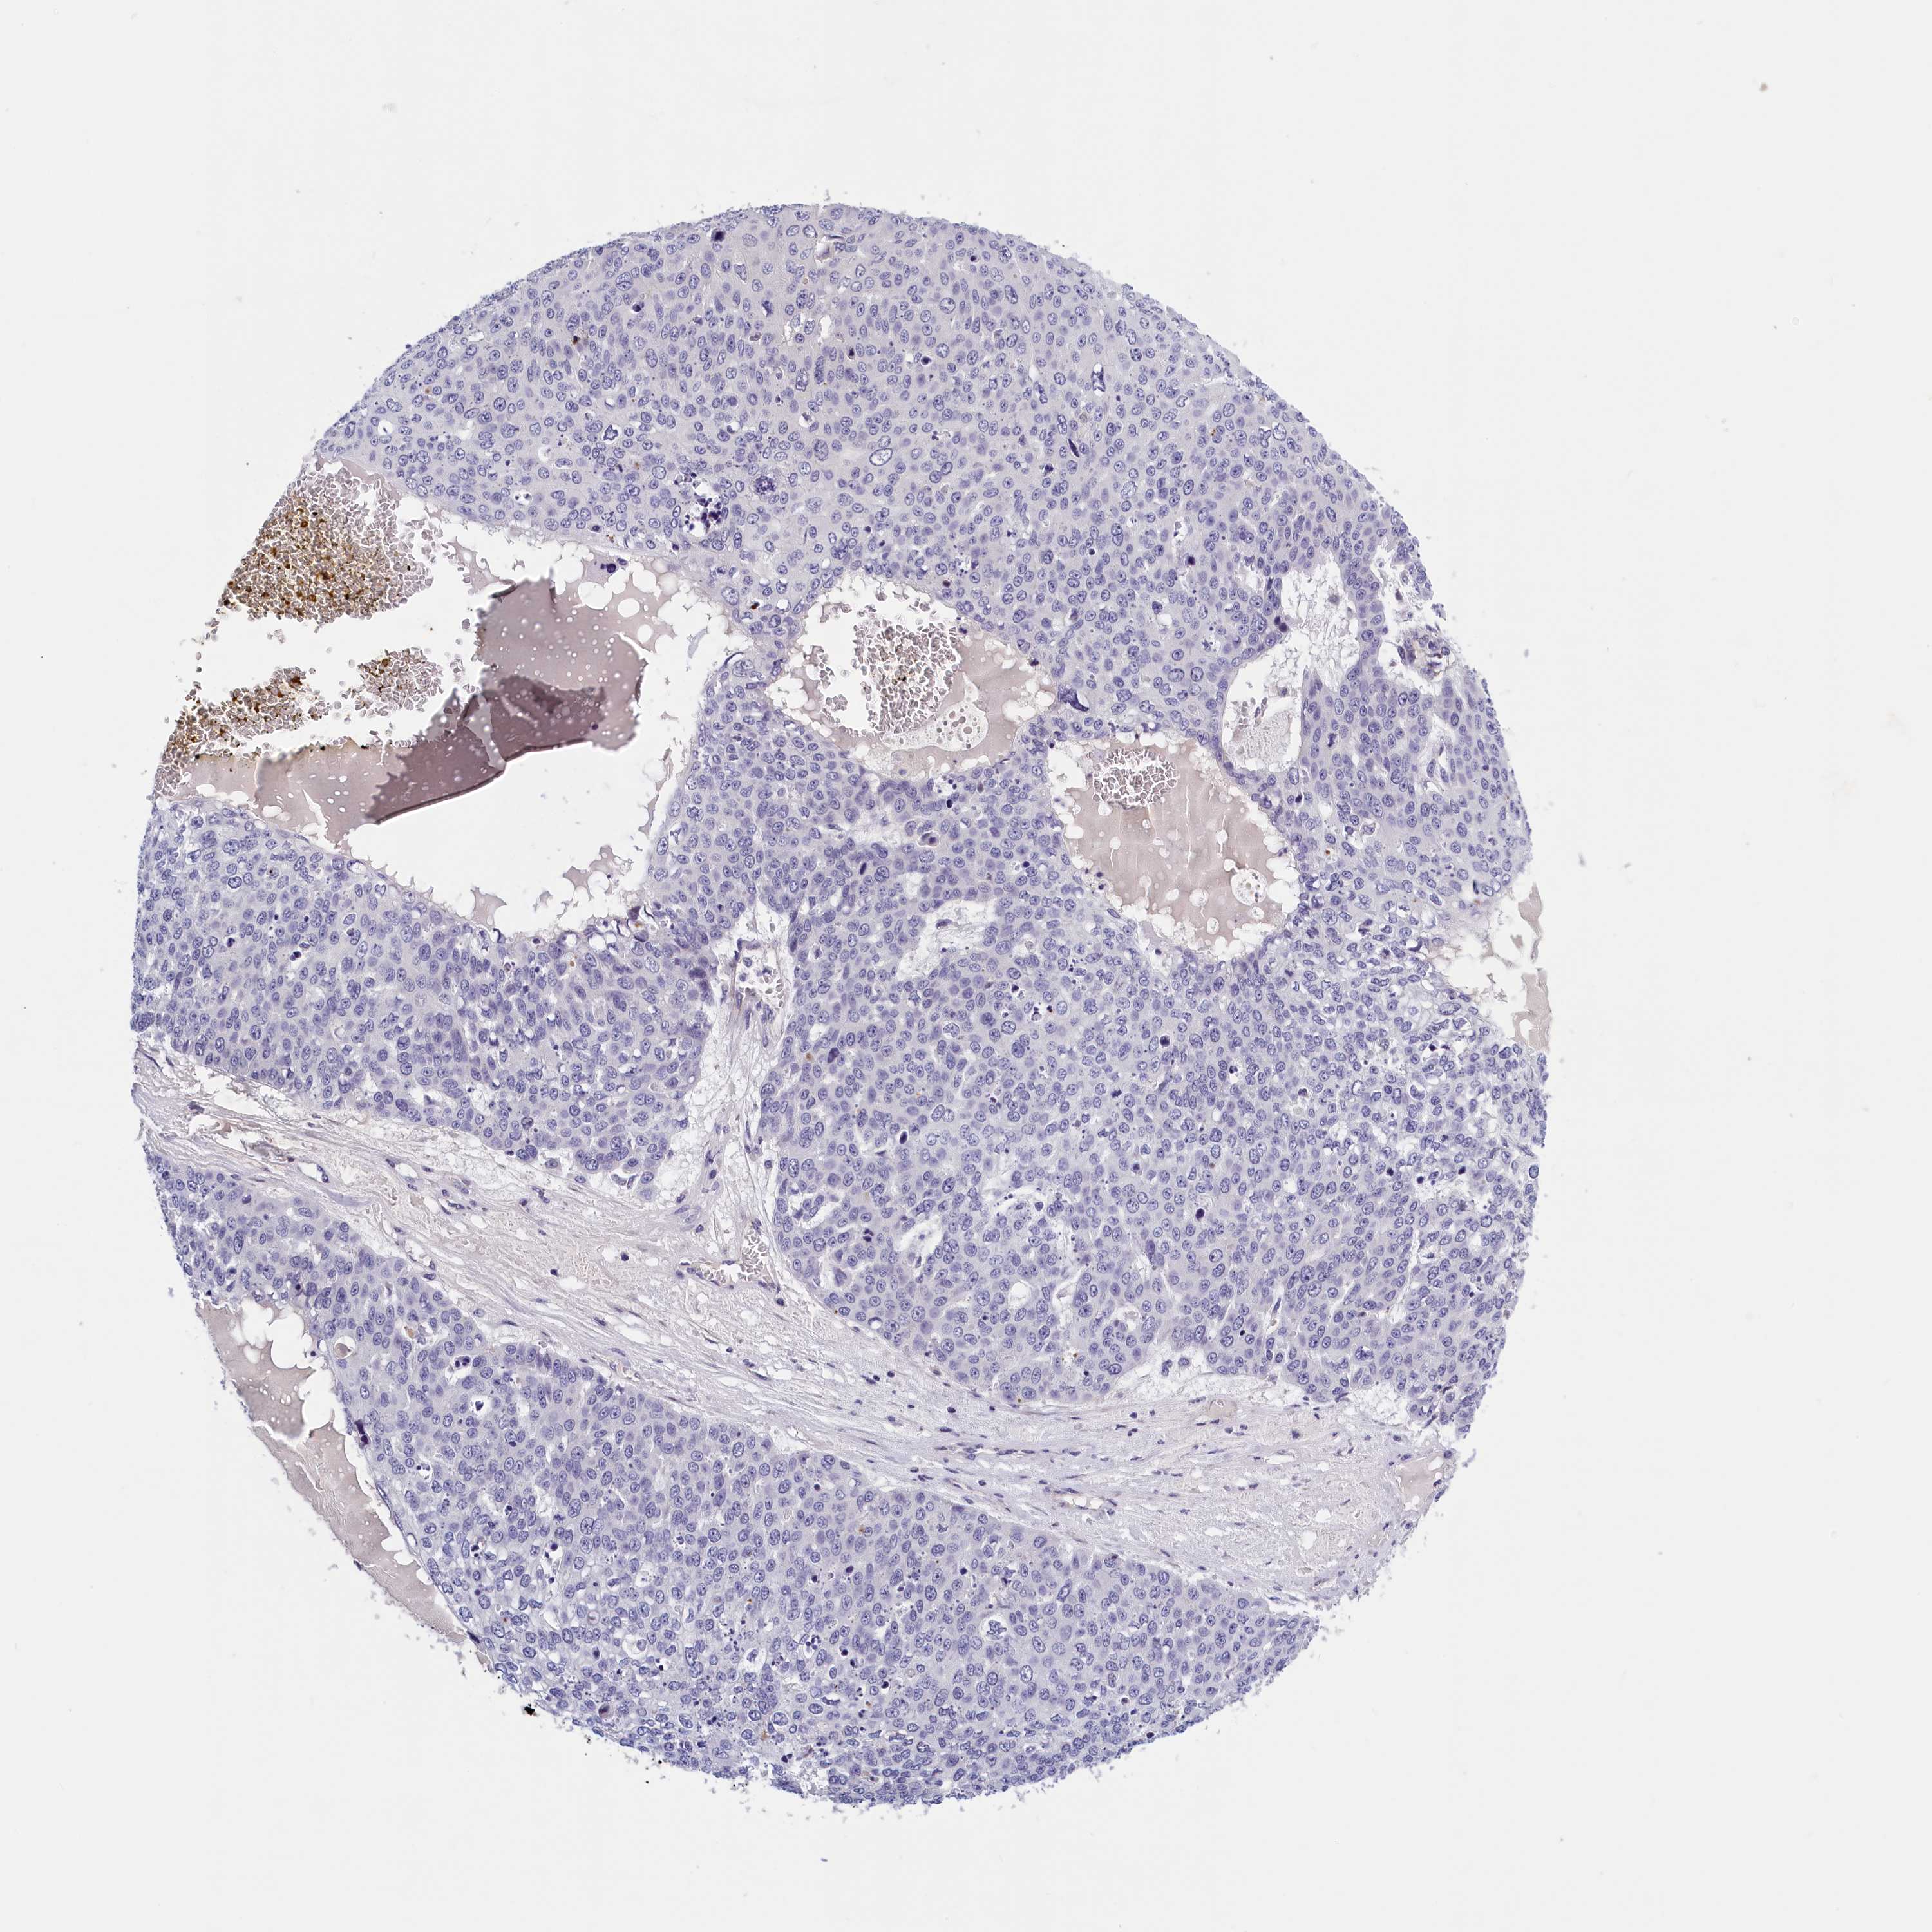

SKIN CANCER - Protein expressioni

A mouse-over function shows sample information and annotation data. Click on an image to view it in a full screen mode. Samples can be filtered based on level of antibody staining by selecting one or several of the following categories: high, medium, low and not detected. The assay and annotation is described here.

Each image is clickable and will lead to virtual microscopy that enables deeper exploration of all samples and also displays staining intensity scores, fraction scores and subcellular localization as well as patient and tissue information for each sample.

Antibody HPA040824

Staining

High

Medium

Low

Not detected

Intensity

Strong

Moderate

Weak

Negative

Quantity

>75%

75%-25%

<25%

None

Location

Nuclear

Cytoplasmic/membranous

Cytoplasmic/membranous,nuclear

Squamous cell carcinoma, metastatic, NOS

Squamous cell carcinoma, NOS